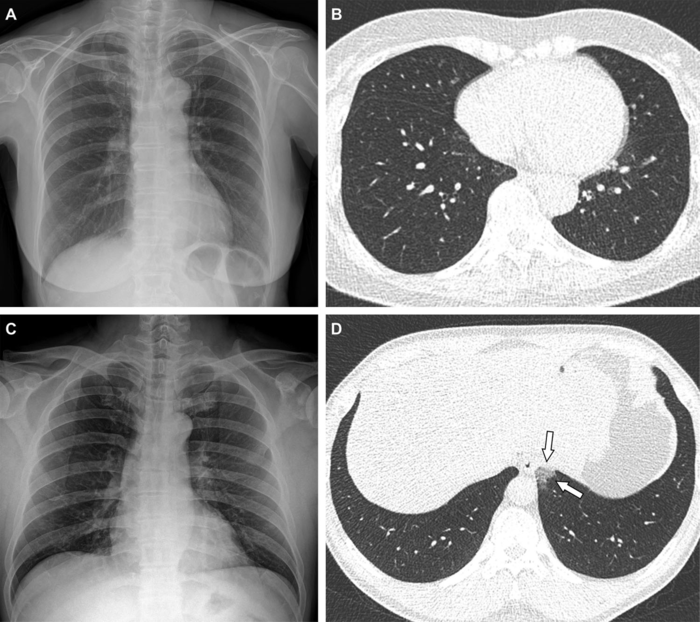

Of the 761 hospitalized patients with COVID-19, the mean age was 47 years, and 385 (51%) were women. Forty-seven patients (6.2%) were fully vaccinated (breakthrough infection), 127 were partially vaccinated (17%), and 587 (77%) were unvaccinated. Chest CT scans were performed on 412 (54%) of the patients during hospitalization. Of patients undergoing CT, the proportion of CT scans without pneumonia was 22% (71/326) of unvaccinated patients, 30% (19/64) of partially vaccinated patients, and 59% (13/22) of fully vaccinated patients. Fully vaccinated status was associated with a lower risk of requiring supplemental oxygen than unvaccinated status, as well as lower risk of intensive care unit (ICU) admission.